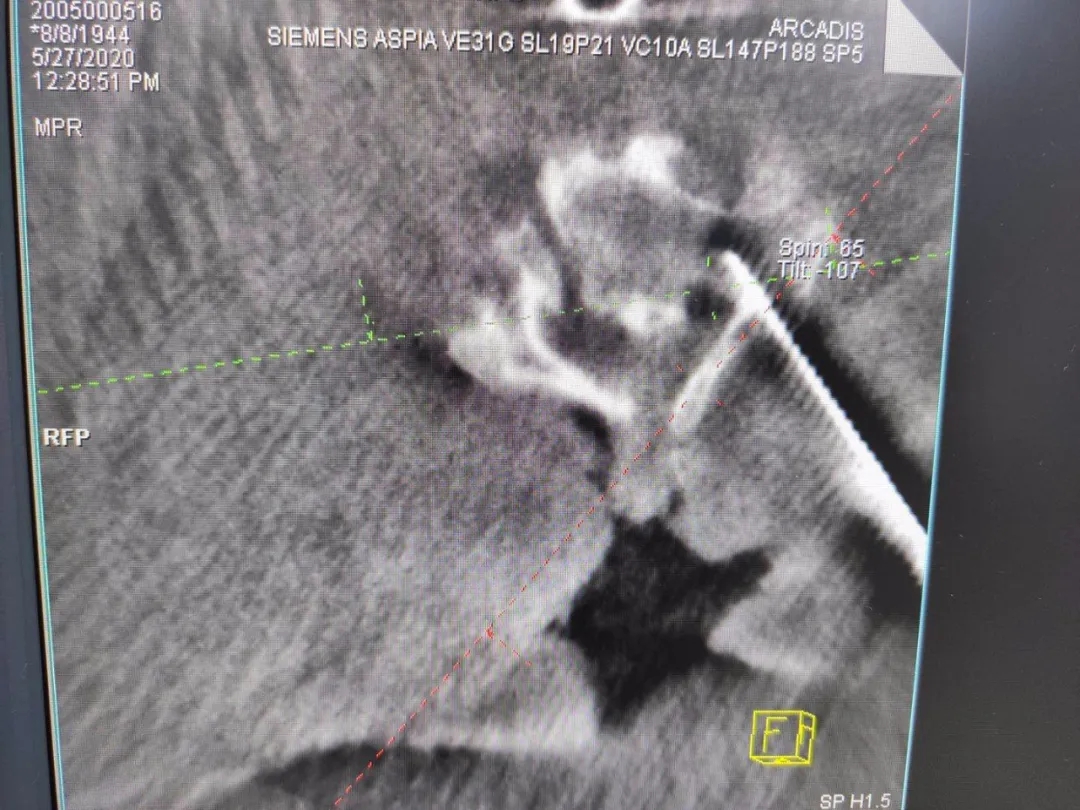

ÊõÖÐÔÚ°²ÅźÃÌå±í¶¨Î»ÒǺó£¬ £¬£¬£¬£¬µÐÊÖÊõ²¿Î»¾ÙÐÐÈýάɨÃ裬 £¬£¬£¬£¬ÍýÏë¾±7×µ¹­¸ùÂݶ¤Öö¤õè¾¶¡£¡£ ¡£¡£¡£¡£¡£

°´Éè¼Æ¾ÙÐÐÖÃÈëµ¼Õë

ÈýάÔÙ´ÎÑéÖ¤µ¼ÕëλÖ㬠£¬£¬£¬£¬Öõ¼¾«×¼

ÔÚÌìçá?¹Ç¿ÆÊÖÊõ»úеÈ˸¨ÖúÏ£¬ £¬£¬£¬£¬Í¨¹ý¾«×¼¶¨Î»£¬ £¬£¬£¬£¬Ò½ÉúΪ·¶°¢ÆÅÖÃÈëÂݶ¤£¬ £¬£¬£¬£¬ÊÖÊõÖмÈûÓÐËðÉ˵½×µ¶¯ÂöҲûÓÐÅö´¥¼¹Ë裬 £¬£¬£¬£¬ÊÖÊõǰºóÖ»ÓÃÁËÒ»¸ö°ëСʱ£¬ £¬£¬£¬£¬³öѪÁ¿ºÜÊÇÉÙ¡£¡£ ¡£¡£¡£¡£¡£